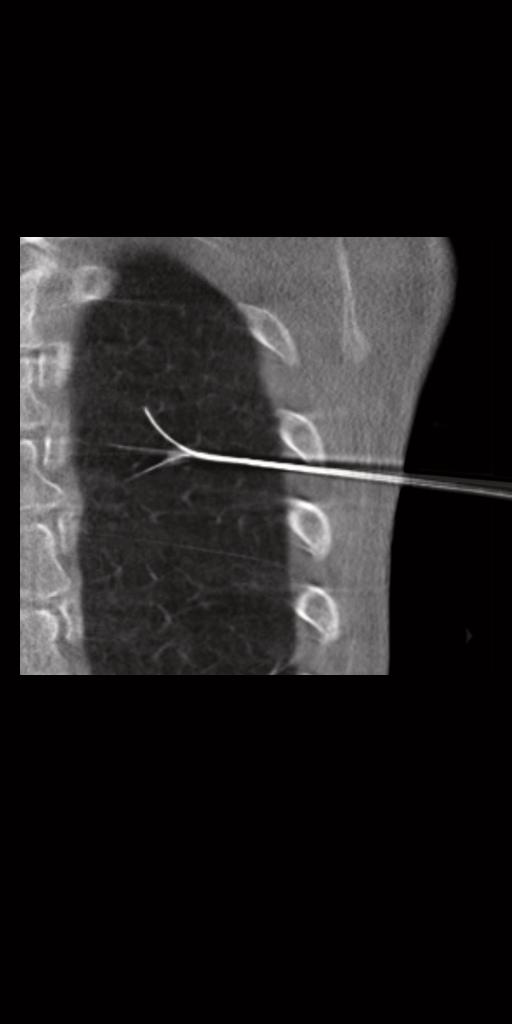

syngo DynaCT

myNeedle Companion harmonise la planification et le guidage des procédures percutanées avec aiguille pour plusieurs modalités. Le flux de travail et l’interface utilisateur sont ainsi unifiés sur les systèmes d’angiographie et TDM. myNeedle Companion permet de réaliser des procédures de routine ou avancées.

Le flux de travail débute avec syngo DynaCT,

qui vous permet de visualiser les lésions et l’anatomie.

Avec l’autorisation de l’hôpital universitaire de Francfort, Allemagne